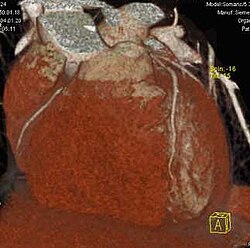

Erst mit der Einführung von Mehrzeilen-Spiral-CTs Mitte der 1990er Jahre gab es in der Computertomographie isotrope Voxel.[1] Da alle heutigen (2011) klinischen CTs kleine isotrope Voxel erzeugen können, ist eine hohe räumliche Auflösung in beliebigen Raumrichtungen möglich. Durch die multiplanare Reformation werden auch sagittale und koronale Darstellungen in hoher Qualität möglich, die für den Nicht-Radiologen erheblich einfacher zu verstehen sind. Die Maximum Intensitäts Projektion stellt die Maximalwerte aus einem frei wählbaren Datenvolumen dar, die auf eine Ebene projiziert werden, vergleichbar einem Schattenbild. Durch die heute auf Auswerte- bzw. PACS-Workstations preiswert verfügbare Rechenleistung können aus den Daten auch hochwertige 3D-Darstellungen in Form von MIP, Surface-Rendering oder – am aufwändigsten und beeindruckendsten – Raycasting erzeugt werden.

Für den Radiologen in der klinischen Routine ist die MIP zur Gefäßdarstellung und der Suche nach Lungenmetastasen sehr hilfreich. Eine 3D-Darstellung ist zur präoperativen Darstellung von Mehrfragment-Frakturen für den Chirurgen nützlich. Raytracing und MIP werden ferner im Rahmen von Spezialanwendungen für Visualisierungen in der Computertomographie des Herzens und der virtuellen Koloskopie verwendet.

CT-Angiographie; mittels multiplanarer Reformation (hier die sog. curved MPR) sind auch Schnittdarstellungen entlang beliebiger Gefäßverläufe möglich, wodurch die gezeigte Arteriosklerose sehr gut visualisiert werden kann.